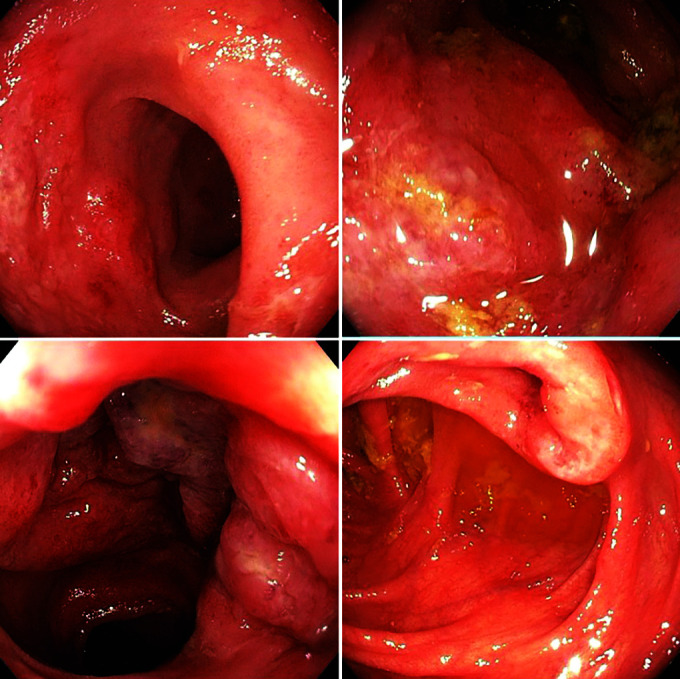

肠热病是东南亚地区的常见病,表现形式多种多样。部分治疗往往会导致病程延长。此外,肠道造影往往会与肺结核相混淆。结肠镜检查和活组织检查有助于与肺结核相鉴别。有关肠热病结肠镜检查的资料很少,而且大多来自胃肠道(GI)出血的病例报告。我们描述了三例肠道热伴有胃肠道受累的病例,其症状与肺结核相似。结肠镜检查的特征是回肠粘膜呈粉蓝色,水肿,扩张性减弱,并伴有多处浅表溃疡。所有三个病例的回盲瓣均受累。两个病例累及升结肠。治疗后随访发现病灶完全消退:Verma A, Dahale AS, Gopal P, et al.模仿科赫氏病的无并发症肠炎结肠镜检查结果。Euroasian J Hepato-Gastroenterol 2024;14(1):120-123.

Enteric fever is a common occurrence in Southeast Asia with a myriad of presentations. Partial treatment often leads to prolonged illness. Along with this, bowel imaging often confounds the picture with tuberculosis. Colonoscopy and biopsy may help to differentiate from tuberculosis. The data on colonoscopy is scarce in enteric fever and is mostly available from case reports of gastrointestinal (GI) bleeding. We have described three cases of enteric fever with GI involvement mimicking tuberculosis. The colonoscopy picture is characteristic of pinkish-bluish ileal mucosa, with edema and decreased distensibility, along with multiple superficial ulcers. The ileocecal valve was involved in all three cases. The ascending colon was involved in two cases. There was complete resolution of lesions after treatment on follow-up.